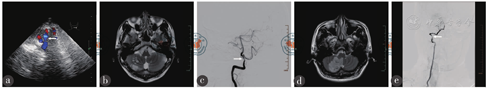

注:a~c图为病例1患者,a为经颅彩色多普勒超声示:右椎动脉V4段双管腔结构(白色箭头处),其中真腔较明亮、假腔较暗淡,真腔与假腔收缩期峰值流速比值>3;b为头颅磁共振示:右侧小脑半球见多发斑片状、斑点状异常信号灶,T2WI呈高信号;c为数字减影血管造影示:右侧椎动脉V4段重度狭窄(>70%)伴局部充盈缺损(白色箭头处);d~e图为病例2患者,d为头颅磁共振示:右侧小脑半球可见斑片状异常信号灶,T2WI呈高信号;e为数字减影血管造影示:右侧椎动脉V2中后段至V3段管腔狭窄扩张不规则,并见局部管腔向外小突起及小片充盈缺损(白色箭头处)

病例1 患者,男,31岁,因头痛、头晕1 d而收住入院。患者于2019年1月16日躺在沙发上玩手机2个多小时后,起身时突感头晕,伴视物旋转、行走不稳、后颈部疼痛,无恶心、呕吐,无黑朦,无复视,无耳鸣及听力下降,约1~2 min后自行好转,遂至当地医院就诊,查头颅CT未见明显异常,就诊过程中再次发生头痛、头晕,伴恶心、呕吐胃内容物4次,予甲磺酸倍他司汀片、异丙嗪等治疗,头痛、头晕无明显改善。为求进一步治疗,来我院就诊,经颅彩色多普勒超声(transcranial color Doppler ultrasound,TCCD)(2019年1月17日)示右椎动脉段V4段探及双管腔结构(图1a),夹层考虑。头颅磁共振成像(magnetic resonance imaging,MRI)(2019年1月17日)示右侧小脑半球多发性脑梗塞(图1b),拟"小脑梗塞、椎动脉夹层"收住。患者既往体健。入院查体:体温37.3 ℃,脉搏74次/min,呼吸21次/min,血压120/79 mmHg(1 mmHg = 0.133 kPa),青年男性,身高170 cm,体质量58 kg,发育正常,营养良好,睡眠胃纳可,大小便无殊,心、肺、腹部查体未见异常,诉后颈部有胀痛,用数字评定量表法(用0~10分代表不同程度的疼痛:0分为无痛,1~3分为轻度疼痛,4~6分为中度疼痛,7~9分为重度疼痛,10分为剧痛)自评疼痛分值为2分;神经系统查体:行走不稳,美国国立卫生研究院卒中量表(National Institute of Health stroke scale,NIHSS)评分1分;辅助检查:血常规、凝血、红细胞沉降率、血同型半胱氨酸、抗中性粒细胞胞浆抗体、抗核抗体、抗心磷脂抗体、病毒标志物、传染病、风湿系列等指标均未见明显异常;数字减影血管造影(digital subtraction angiography,DSA)(2019年1月18日)示右侧椎动脉V4段重度狭窄(71%),长度约18 mm(图1c),动脉夹层首先考虑;入科后给予皮下注射4 100 U低分子肝素,每12小时注射1次,5 d后头痛、头晕症状消失,7 d后停用抗凝药物,给予硫酸氢氯吡格雷片75 mg(1次/d)、拜阿司匹林100 mg口服(1次/d),12 d后出院。1个月后面对面随访,无任何不适现象,查体无殊。

病例2 患者,男,24岁,因头晕、行走不稳5 d而收住入院。患者于2019年1月4日晚上趴在床上看电影2 h,起身后突发头晕、行走不稳,伴枕部胀痛、恶心、呕吐(呈非喷射性),无意识障碍,无肢体麻木,无听力下降,无视物旋转,无胸闷、心悸等。至当地医院就诊,颅脑MRI检查示:右侧小脑半球异常信号,考虑脑梗塞可能性大,建议转至上级医院治疗。遂于2019年1月8日至我院急诊就诊,拟"急性右侧小脑梗塞"于1月9日收住神经内科。患者既往除有颈椎病史数年,表现为颈肩部酸胀外,余身体健康。入科查体:体温36.5 ℃,脉搏78次/min,呼吸19次/min,血压137/95 mmHg,青年男性,身高178 cm,体质量78 kg,发育正常,睡眠胃纳可,大小便无殊,心、肺、腹部查体未见异常;神经系统查体:右眼凝视眼震,行走不稳,NIHSS评分1分;辅助检查:血常规、凝血、红细胞沉降率、血同型半胱氨酸、抗中性粒细胞胞浆抗体、抗核抗体、抗心磷脂抗体、病毒标志物、传染病、风湿系列等指标均未见明显异常;头颅MRI(2019年1月11日)示右侧小脑梗塞(图1d);DSA(2019年1月10日)示右侧椎动脉V2中后段至V3段管腔狭窄扩张不规则,并见局部管腔向外小突起及小片充盈缺损(图1e),夹层考虑;入科后给予拜阿司匹林100 mg(1次/d)、硫酸氢氯吡格雷片75 mg(1次/d)、甘油果糖250 mL(每12小时给药1次)治疗,3 d后停用阿司匹林,治疗5 d后眼震消失、行走正常,1周后出院。1个月后电话随访,无任何不适现象。